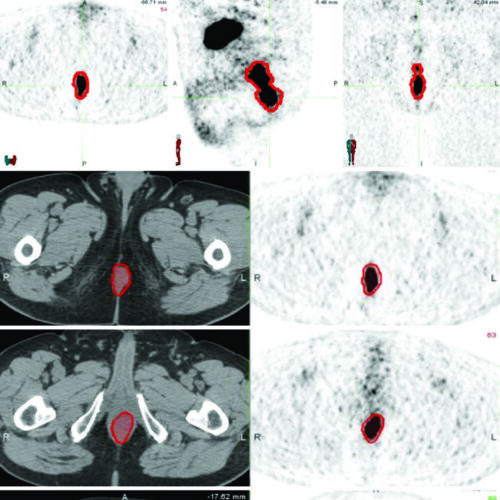

Delineamento de Volumes

Guias práticos de delineamento de volumes-alvo e órgãos de risco por sítio anatômico na radioterapia.